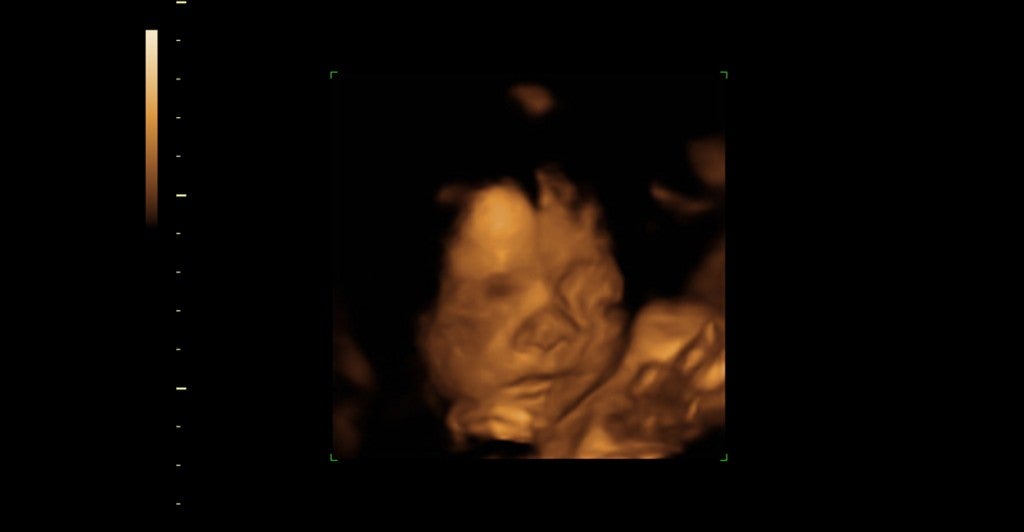

Renee Lee’s tragedy provided the impetus for the law. Lee, a young woman dealing with an unexpected pregnancy, was duped into taking the abortifacient drug, Misoprostol, by her boyfriend, John Welden. Immediately Welden faced conviction, not for murder, but for “tampering with a consumer product.”

At the passage of the law, an emotional Lee told Reuters, when you “[want] that baby and someone violently takes it from you – it needs to be a crime.”